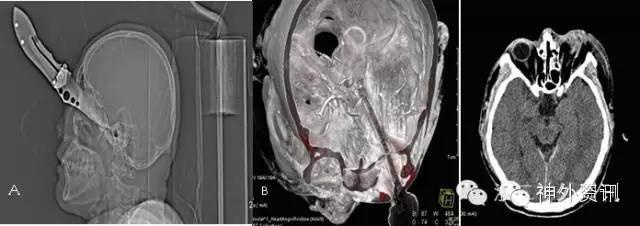

头颅CT提示:可见金属棒状物自右颈部颌下斜行经口咽、左侧鼻咽及中颅底,至左侧额颞部颅骨穿出,伴右侧颌下及上颈部皮下气肿,周边放射状伪影明显,周围结构显示欠清,左颞叶脑实质穿透,异物周边脑实质水肿,右侧脑室受压变形,局部中线结构轻度右偏。左顶部头皮软组织肿胀。左侧中颅底及左顶骨骨折,鼻骨骨折(见图2)。

图2. 头颅CT提示螺纹钢与左颈内动脉管贴近,最近处约2mm(箭头所示)。

颈动脉CTA示:两侧颈动脉周边未见明确血肿,金属异物与左颈内动脉管贴近(见图 3)。

图 3. 三维重建显示螺纹钢位置。